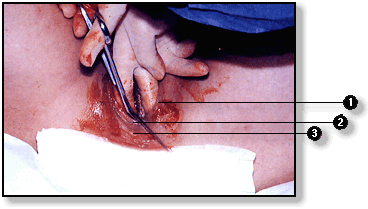

Momento del parto en el cual la cabeza fetal está emergiendo a través del canal del parto. La línea segmentada muestra el sitio donde se practica la episiotomía, insición quirúrgica que previene la ruptura de los músculos del periné.